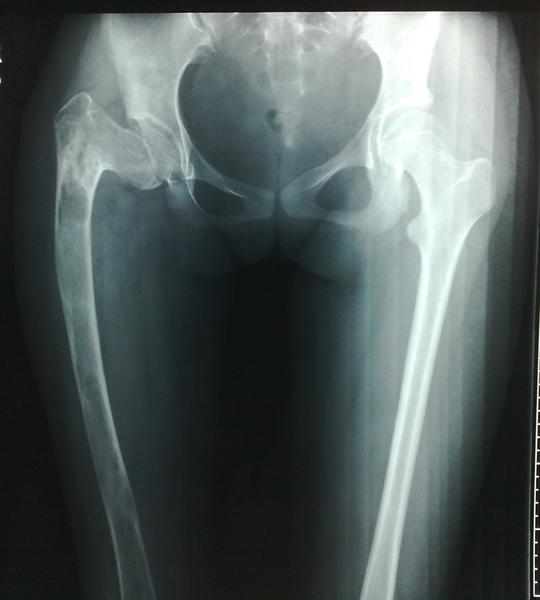

重度髋内翻粗隆下截骨全髋关节置换术

股骨近端骨纤维结构不良严重内翻畸形的矫形治疗